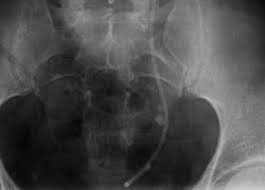

Urogram x ray of the abdomen in a 32 year old patient showing polycystic kidney disease affecting both kidneys at upper left and right bilateral.